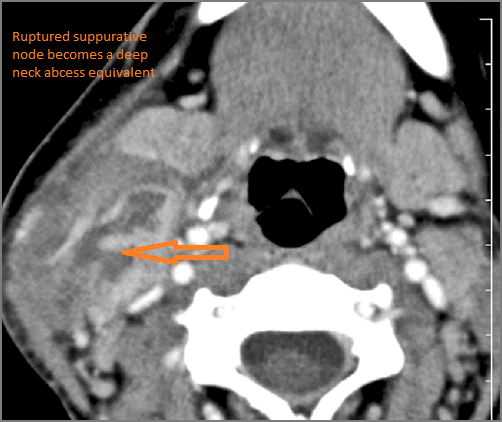

1-year old with fever, difficulties feeding and possible retropharyngeal abscess.Exam

Contrast-enhanced CT of the maxillofacial region and neck and related anatomy with images obtained in the balanced or venous vascular phase to ensure optimal visualization of both arterial and venous structures as well as possible reactive changes around infected collections. 0.5-3.0 mm thick sections were obtained in the axial plane and reformatted 3D and/or in the coronal and sagittal planes and viewed inter actively in 3 dimensions at the computer work station.